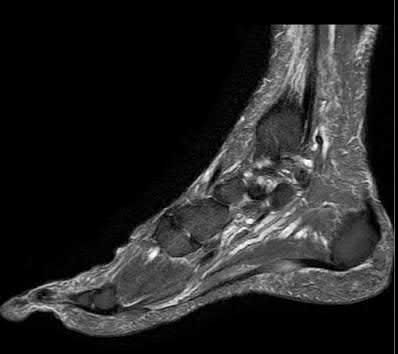

A 25-year-old male sustains an ankle fracture dislocation and undergoes open reduction and internal fixation. He returns to clinic five months following surgery complaining of continued ankle pain and instability with weight bearing. His immediate post-operative AP radiograph is seen in Figure A. Which of the following could have prevented this patient from developing persistent pain?

The patient presents with continued ankle pain and instability following open reduction and internal fixation. The radiograph in figure A demonstrates inadequate restoration of fibular length, likely leading to continued tibiotalar instability.